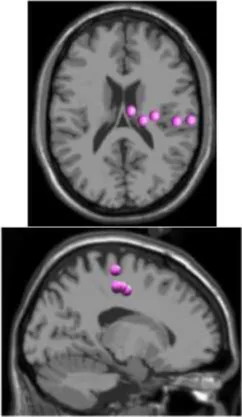

As expected the average treadmill belt velocity was more variable during active treadmill walking, regardless of command speed (Figure 3A). Average pelvis velocity in the sagittal plane was similar for the slow and fast walking commands, indicating the participants were able to match the desired treadmill command speed accurately during the steady walking tasks (Figure 3B). The k-means clustering resulted in seven spatially distinct clusters of electrocortical dipole sources, plus one additional outlier cluster (Table 1). We identified the Brodmann areas represented within each cluster from the Talairach atlas (Lancaster et al., 2000); dipoles were located within ±3 mm cube range of 14 Brodmann areas across the seven clusters. We performed spectral and time-frequency analysis on 6/7 clusters with the RPM cluster omitted because it did not contain ICs from a majority of the participants.

Table 1

| Posterior parietal | Left motor | Right motor | Left premotor | Right premotora | Anterior cingulate | Prefrontal | |

|---|---|---|---|---|---|---|---|

![]() | ![]() | ![]() | ![]() | ![]() | ![]() | ![]() | |

| Number of subjects | 7 | 5 | 5 | 5 | 3 | 5 | 5 |

| Number of ICs | 9 | 5 | 5 | 5 | 4 | 5 | 5 |

| Brodmann areasb | 5, 7, 31 | 3, 4, 31 | 1, 3, 4, 6 | 6, 8, 24 | 6, 24 | 24, 32, 33 | 9, 10, 32, 46 |

Clusters of dipolar sources fit to independent components.

aThe RPM cluster was omitted from analysis because it did not contain ICs from a majority of the subjects.

bBrodmann Areas reflect those found within a ±3 mm search range of all individual dipoles within a cluster.